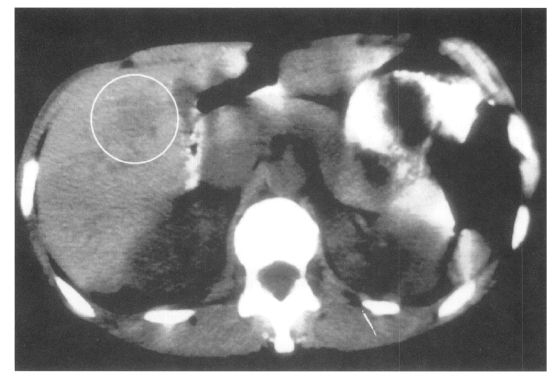

Medical imaging techniques can be used to detect and localize granulomatous lesions due to Toxocara larvae. Abdominal ultrasound has shown multiple hypoechoic areas in the livers of 14 children who initially presented with hepatomegaly, eosinophilia and a positive Toxocara serology (Baldisserotto et al., 1999). Using computed tomography (CT), hepatic lesions appear as low-density areas, as shown in Fig. 1 (Dupas et al., 1986; Ishibashi et al., 1992). In the CNS, more sensitive magnetic resonance imaging (MRI) has revealed granulomas appearing as hyper-intense areas on T2-weighted images, primarily located cortically or sub-cortically (Ruttinger and Hadidi, 1991). In 11 patients with OLM, ultrasound has revealed a highly reflective peripheral mass, vitreous bands or membranes, and traction retinal detachment (Wan et al., 1991).

Liver CT scan showing a low-density area (circled) due to toxocariasis